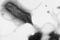

ぜひ自分のピロリ菌ステータスの把握を(写真はイメージ)